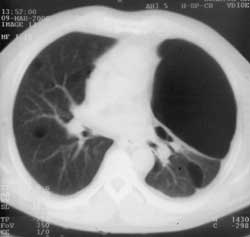

Преимущества рентгеновской компьютерной томографии в диагностике буллезной болезни легких.

Рис. 2. На компьютерной томограмме того же больного хорошо видна тонкостенная полость. В паринхиме обоих легких так же тонкостенные буллезные полости.